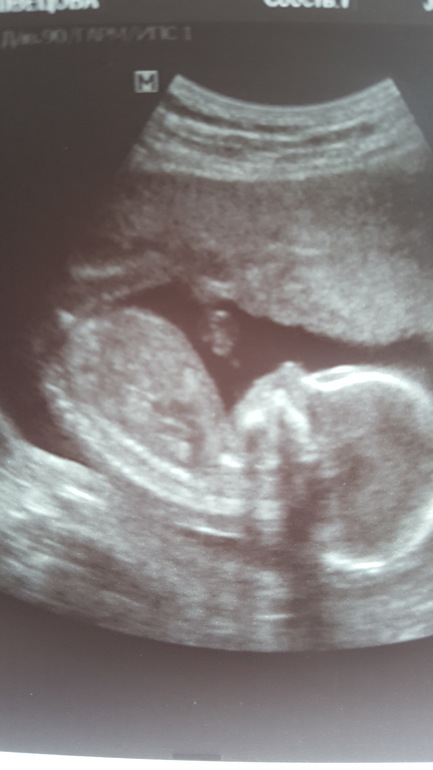

17 недель

УЗИ, КТГ, доплерпуская пузыри живем мы беззаботно 👼😂

и весим уже 206 грамм

сходили на узи все ок, несмотря на мой герпес и орз на антибиотиках (прошло с момента простуды 1,5 недели).

делали через живот, но так как я худая удалось всё-такимю измерить шейку! ура...радует 38,7мм. (вагинально не стали смотреть из-за герпеса).

о и да, мы лежим головой вниз! второе ура! так как 2 недели назад лежали поперек.

прибавили за 2 недели 81 грамм!)

воды хорошие, чистые. кровоток тоже в норме.

опережаем срок на 3 дня.

нос у нас уже 5мм)))

до сих пор низкая плацентация, но уже на 2,7 см выше вн.зева.

папа наш уезжает на 2 недели поэтому настоял на узи

..посмотреть на дочу)))